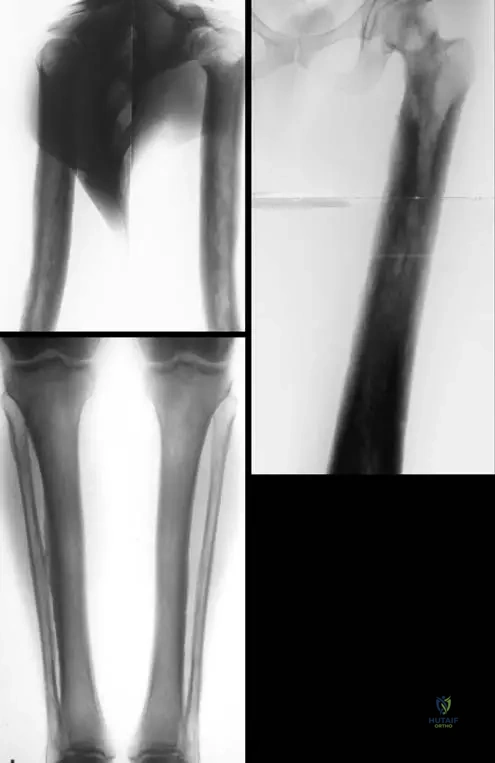

Rationale: The teaching case explicitly states that Progressive Diaphyseal Dysplasia "is an autosomal dominant disorder involving the diaphyses of the long bones, skull base, and clavicles." The radiographic images (Fig. 1.120) also clearly show cortical thickening and sclerosis in the diaphyses. Therefore, the diaphyses (D) are the primary affected part of the long bones.

Rationale: Fig. 1.122 a–d shows "Definitive, late form of progressive diaphyseal dysplasia on anteroposterior radiographs of skull (a), hand (b), arm (c), forearm (d)". The image specifically includes a radiograph of the hand (b), demonstrating involvement of the metacarpals and phalanges. The other options are not explicitly shown or mentioned as affected in the provided images/text.

Rationale: Fig. 1.120 a–c is captioned: "Diaphyseal cortical thickening and sclerosis of long tubular bones are the main characteristics of Camurati-Engelmann disease." The images clearly illustrate this feature in the humerus, femur, tibia, and fibula. Options A, B, D, and E describe features not seen in the provided images or characteristic of this disease.

A 40-year-old male with a long-standing diagnosis of Camurati-Engelmann disease undergoes a skeletal survey. The radiographs show extensive sclerosis and cortical thickening. Which of the following images represents a definitive, late form of this condition, demonstrating involvement beyond just the long bone diaphyses?

Correct Answer: C

Rationale: Fig. 1.122 is specifically labeled "Definitive, late form of progressive diaphyseal dysplasia on anteroposterior radiographs of skull (a), hand (b), arm (c), forearm (d)." This image directly shows sclerosis in the skull and hand bones, which are areas mentioned in the text as being involved in the disease (skull base, and by extension, other skull bones can be affected, and hand bones are shown in the image). The other options describe findings inconsistent with Camurati-Engelmann disease.